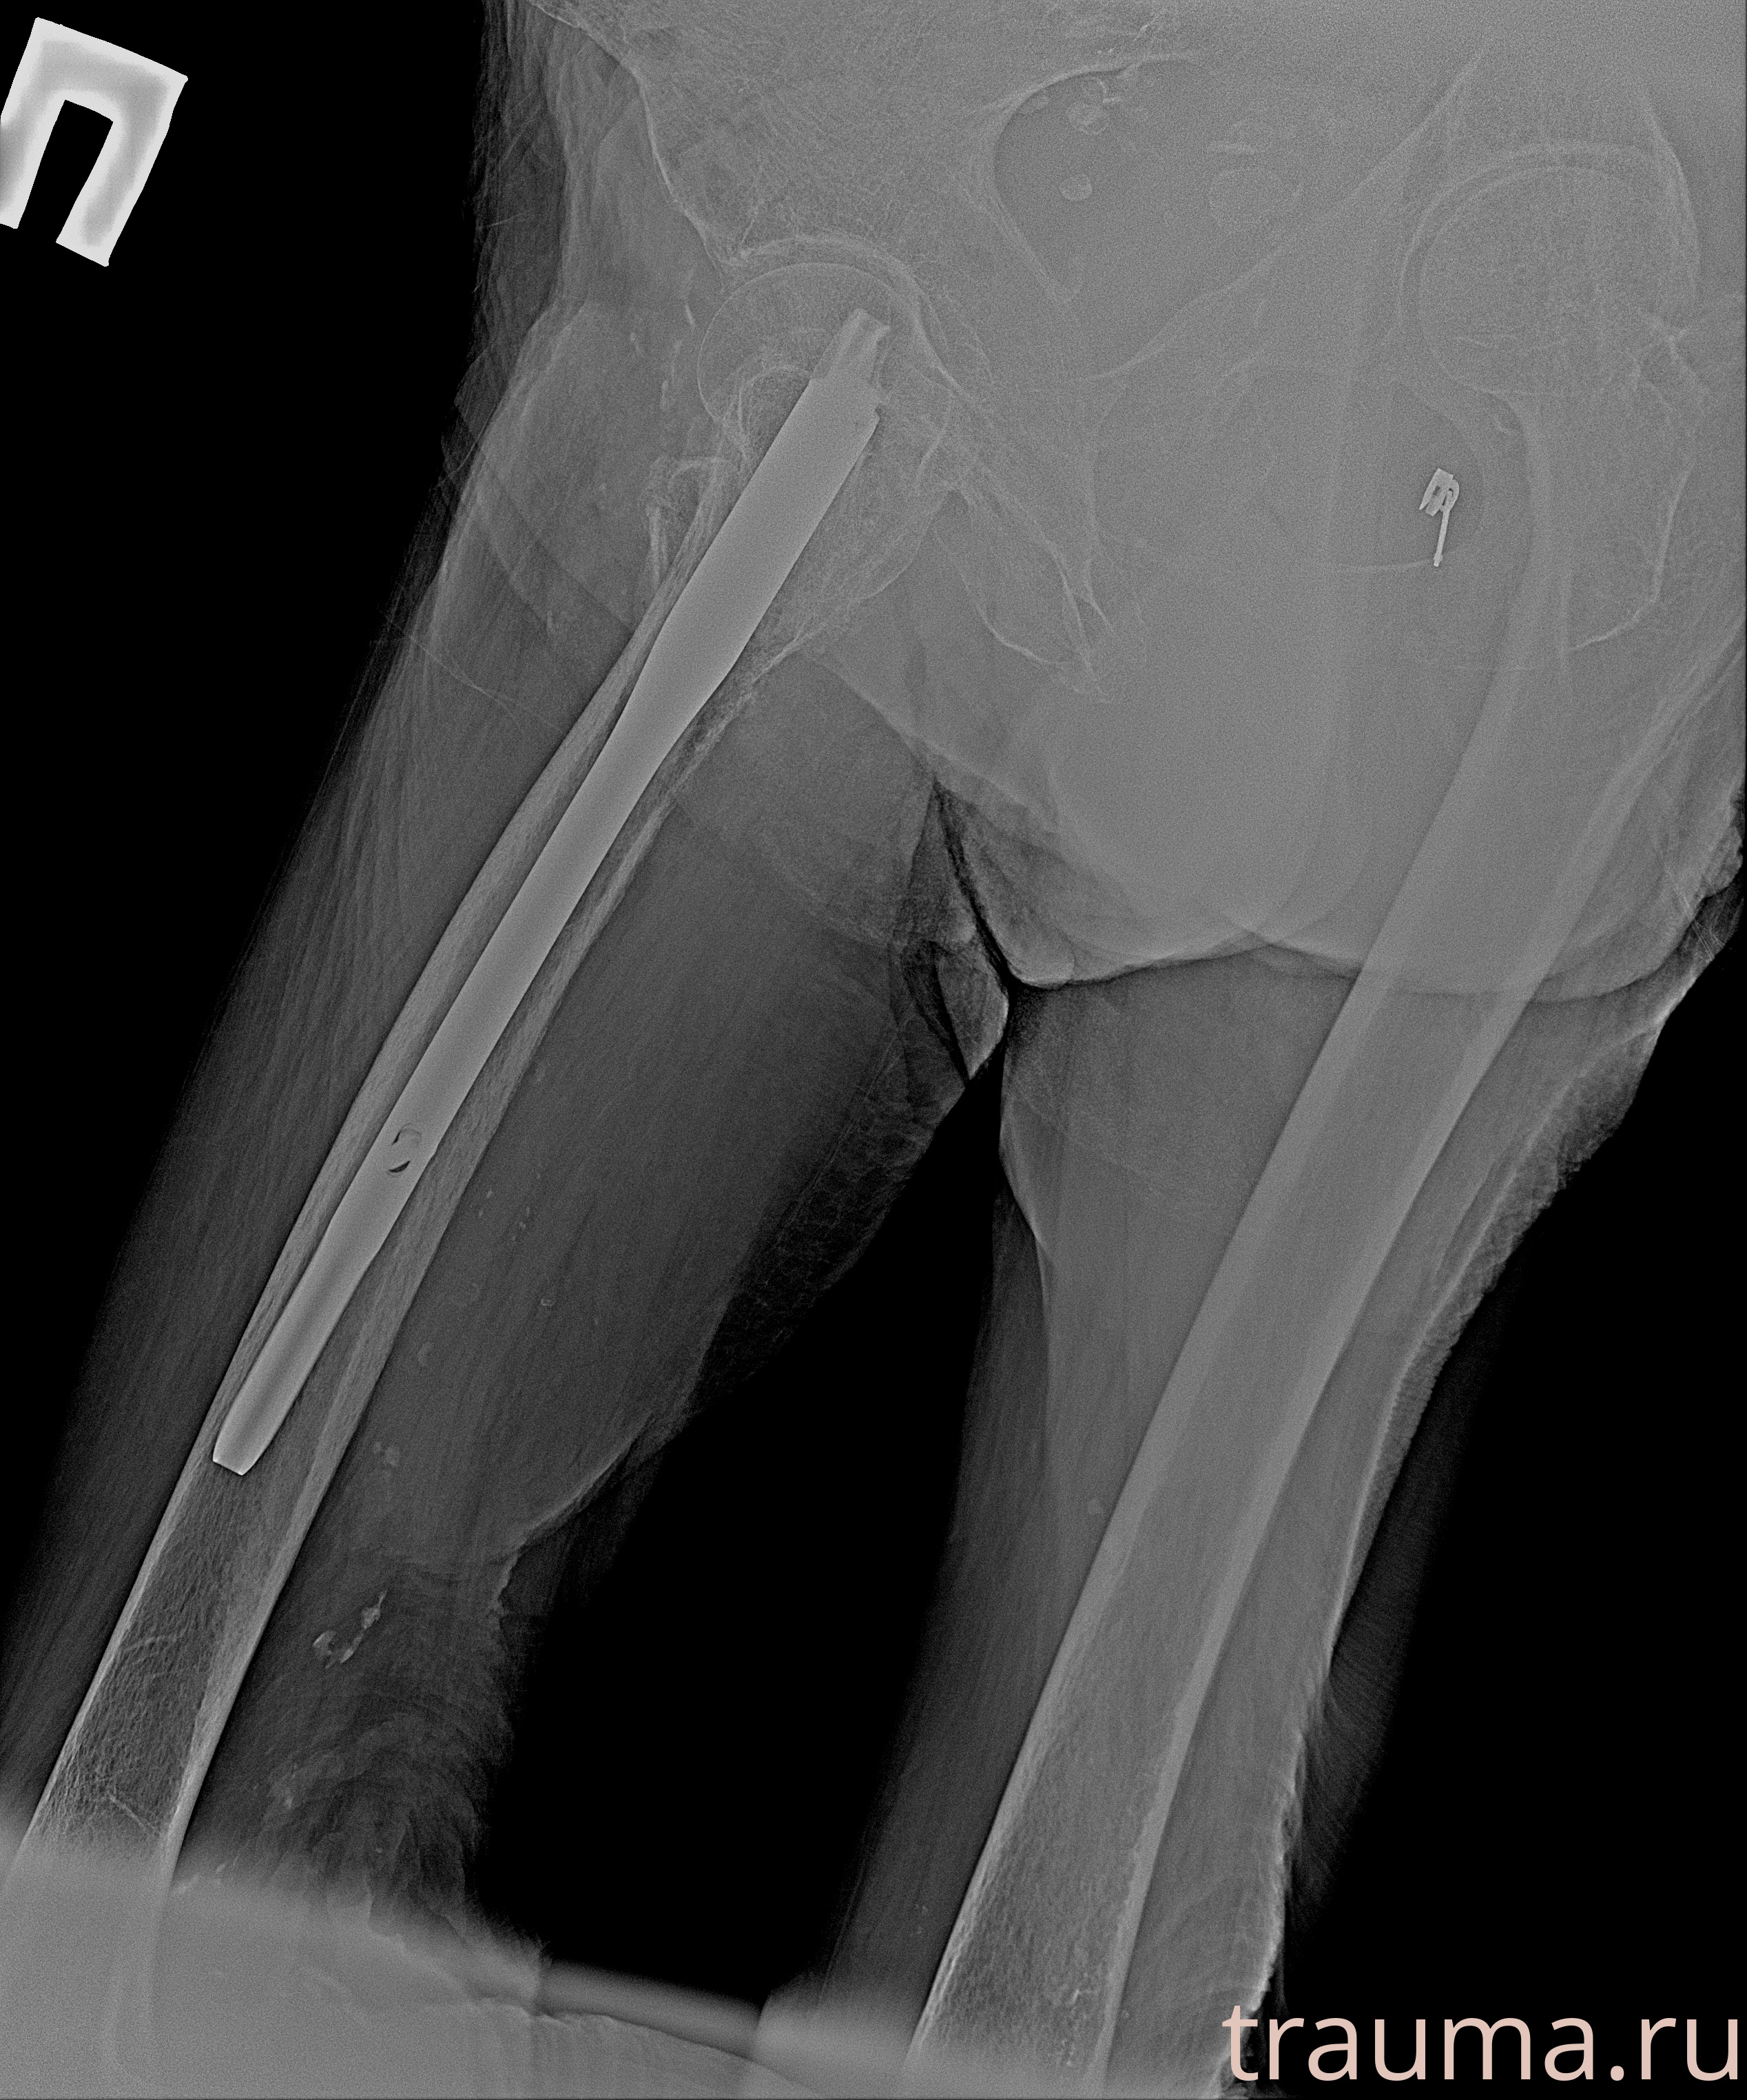

Рентгенограммы

Рентген на дому: по вашему адресу приезжает врач-рентгенолог, травматолог-ортопед с мобильным рентгеновским аппаратом, проводит диагностику травмы или заболевания, делает необходимые рентгенограммы, дает рекомендации по дальнейшему лечению. Получить качественные снимки в домашних условиях возможно благодаря уникальной методике, разработанной МосРентген Центром для института  Склифосовского